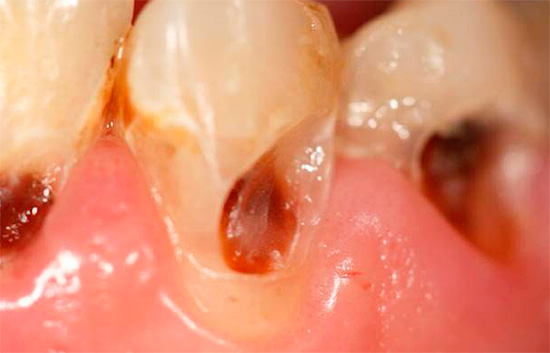

Abaixo estão algumas fotos com exemplos de cárie cervical:

A foto a seguir mostra claramente a cárie profunda na região cervical: